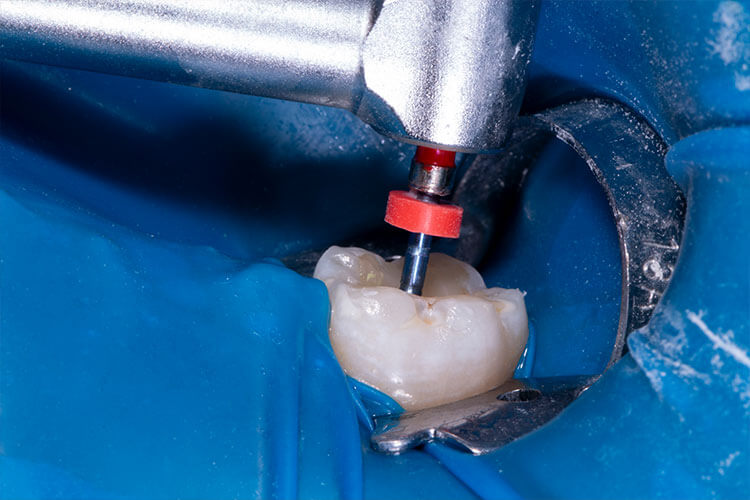

COROAS E FACETAS EM CERÂMICA |

COROAS E FACETAS EM CERÂMICA |